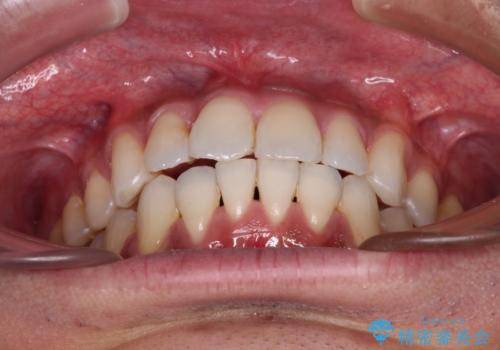

- 上下前歯の叢生を気にして来院された患者様です。

奥歯はクロスバイトとなっているので上顎は側方拡大を行いつつ、上下全体の叢生をインビザラインにより改善することとしました。

治療途中でクリーニングやホワイトニングを行い、歯列が整うと同時に明るい口元となりました。